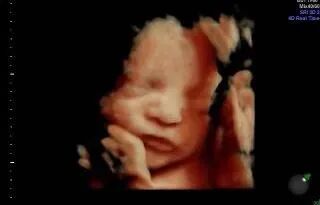

爱妈B已接近孕期的第37周,宝宝几乎已经准备好迎接这个世界。通过最近的B超,我们可以清楚地看到宝宝的面容,非常可爱。宝宝的体重约为6.5磅,身长在19到20英寸之间。他们的肺部和大多数重要器官已经发育成熟,准备在出生后立即发挥功能。尽管在子宫内的空间越来越小,宝宝的活动—如翻身或踢动—依然频繁,有时这些动作会给爱妈带来一些不适。